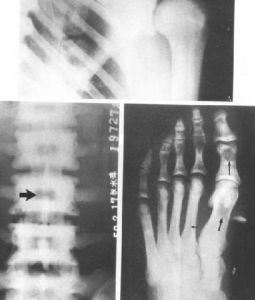

臨床上,症狀多輕微,局部可有輕壓痛或肌肉痙攣。X線和CT上,髂骨耳狀面下均勻性高密度硬化,骨結構不清,骨小梁間隙消失,內緣以骶髂關節。骨質硬化區表現為三角形、新月形或梨形,尖端向上,寬基向下。

範圍病變範圍不一,可累及耳狀面的全部或中下2/3,亦可僅限於中1/3或下1/3。椎體也可發病,多位於腰椎前上角,以L4、L5多見,多單發,亦可累及多個椎體,表現位椎體前上緣三角形緻密影,椎間縫正常。部分病例經隨訪觀察病變範圍可縮小,骨硬化密度減低,但多數無任何改變。

X線檢查:病變在骶髂關節的骼骨耳狀面上出現骨質呈均勻性密度增高,骨小梁消失,邊緣模糊,不侵犯關節面,病變寬度約0.5~3.0厘米,濃白實密徵象。其骨質硬化區構成各種不同的形態,大體上分為三角形、新月形、梨形三種。

X線所見:骶髂關節正位片見關節間隙整齊清晰,靠近骶髂關節面中下2/3的髂骨側骨質異常緻密呈均勻一致的骨質緻密帶,骨小梁紋理完全消失,邊緣清晰但無骨質破壞,不侵犯骶骨側。這種病變多為對稱性,也可發生於單側。局部可呈三角形,新月形或梨形。硬化區可寬達3cm。